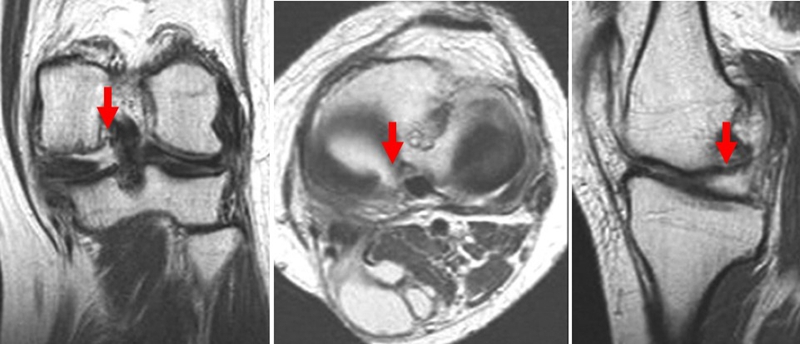

SONK与内侧半月板突出的相关研究中,100%(104)SONK中都有半月板突出,4个SONK在发病前因膝关节疼痛体检发现半月板突出,几个月后通过MRI检查显示存在 SONK。

研究证明半月板挤压是SONK的发病机制之一,半月板挤压的进展可能与SONK的发展有关。

早期(3月内)内侧半月板相对挤压百分比≥33%,是SONK发病1年后预后不良的预测指标,MRI检查没有局灶性轮廓塌陷和髁深处没有低信号线(隔离带),预后好,股胫角>180°(下肢力线内翻>6°)和MRI上深度>20mm 预示SONK患者症状发作后1年预后不良。

内侧半月板挤压(MME)以绝对值和挤压相对百分比 (RPE) 的形式呈现,其定义为挤压半月板宽度与整个半月板宽度相比的百分比

a.患者,59岁女性,AP侧位片显示SONKⅠ期,FTA<180°;b.MRI T2显示病变深度<20mm,患者出现症状1年后保守治疗;c.75岁女性,X线显示SONKⅠ期,FTA>180°;d. MRI T2显示病变深度>20mm,患者于症状出现后11周行手术治疗

影响保守治疗效果的因素